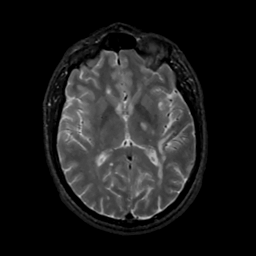

MR Study #15, June 9, 1991 -- Slice #26